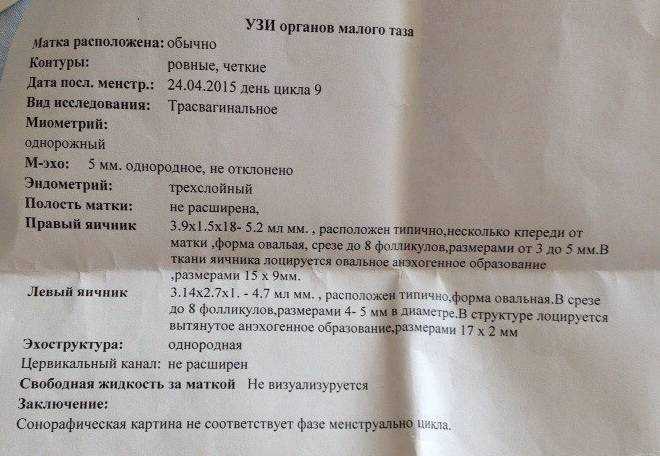

УЗИ малого таза

УЗИ органов малого таза в норме

Почему разные заключения на УЗИ?